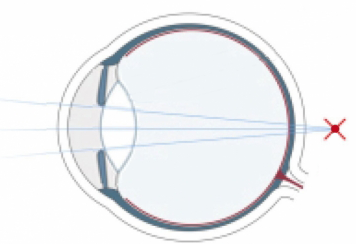

Wer unscharf sieht, war bisher gezwungen, sich mit Brillen und Kontaktlinsen zu behelfen. Die Refraktive Chirurgie ist mit dem LASIK-Verfahren in der Lage, die Sehschwäche am Auge selbst zu korrigieren. Das LASIK-Verfahren hat sich als die erfolgreichste und weltweit am häufigsten angewandte Methode zum Augenlasern etabliert.

Bei Kurzsichtigkeit, Weitsichtigkeit und Alterssichtigkeit sowie bei einer Hornhautverkrümmung setzen wir einen Augenlaser ein, der sich auf dem allerneuesten Stand der Technik befindet. Das Augenlasern führen wir ambulant durch, der Eingriff selbst dauert nur wenige Minuten. Welche Methode beim Augenlasern zum Einsatz kommt, wie sich der Ablauf beim genau gestaltet und welche Kosten hierdurch entstehen, ist abhängig von der vorliegenden Fehlsichtigkeit.